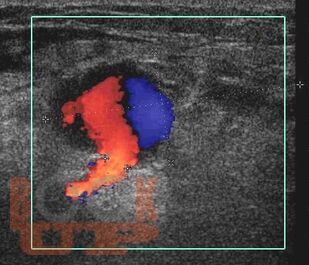

Учебное пособие содержит материал, отражающий представления об эпидемиологии, этиопатогенезе ятрогенных и инфицированных ложных аневризм магистральных артерий. Изложены современные методы клинико-лабораторной и инструментальной диагностики этой когорты пациентов. Освещены результаты хирургической тактики при лечении данной

патологии.